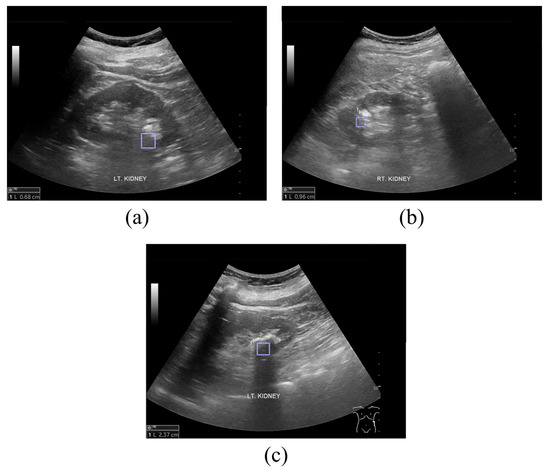

Quantitative Evaluation of Kidney and Gallbladder Stones by Texture Analysis Using Gray Level Co-Occurrence Matrix Based on Diagnostic Ultrasound Images

2.1. Ultrasound Image Acquisition